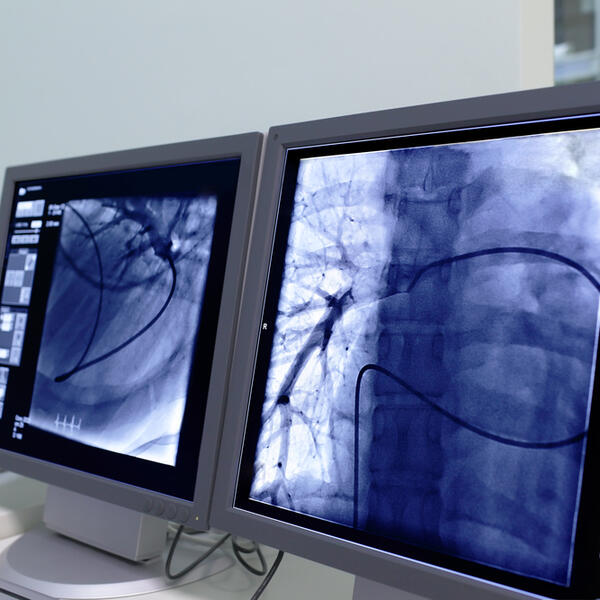

U Kliničkom centru Crne Gore (KCCG) ne postoji stalno dostupna terapija za tretiranje srčanog udara, pa tako u večernjim satima i vikendom nije moguće uraditi kateterizaciju i ugradnju stentova.

Kateterizacija i ugradnja stentova je jedna od najsavremenijih metoda liječenja infarkta i koristi se u svim razvijenijim medicinskim centrima.

Terapija za tretiranje srčanog udara, takozvana primarna PCI, često je spasonosna, i jedina koja može odmah da otvori ciljano arteriju koja je prouzrokovala infarkt.